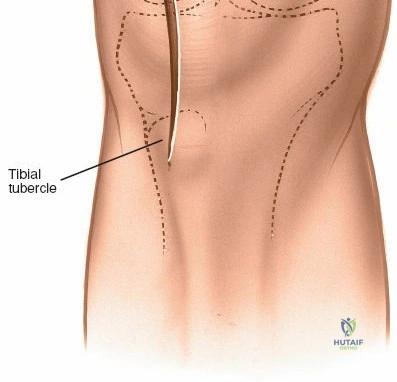

1. Skin Incision

The incision typically begins approximately 3-5 cm proximal to the superior pole of the patella, curves slightly medially along the patellar border, and extends distally parallel to the medial border of the patellar tendon, terminating approximately 2-3 cm distal to the tibial tubercle. A straight midline longitudinal incision is an alternative, particularly when combined with a medial parapatellar capsular approach for TKA, offering a large exposure. The length and curvature of the incision are tailored to the specific procedure and patient anatomy.

Initial skin incision marked, extending proximally along the quadriceps, medially to the patella, and distally along the patellar tendon.